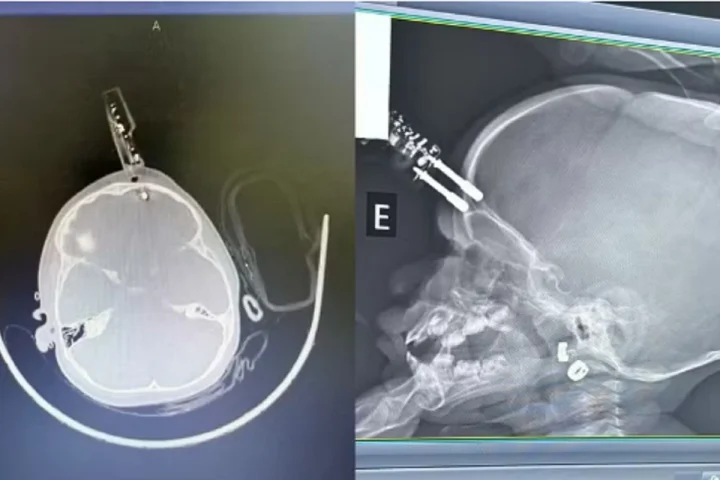

O objeto perfurou o crânio da criança, que segue internada sem sinais de sequelas neurológicas imediatas.